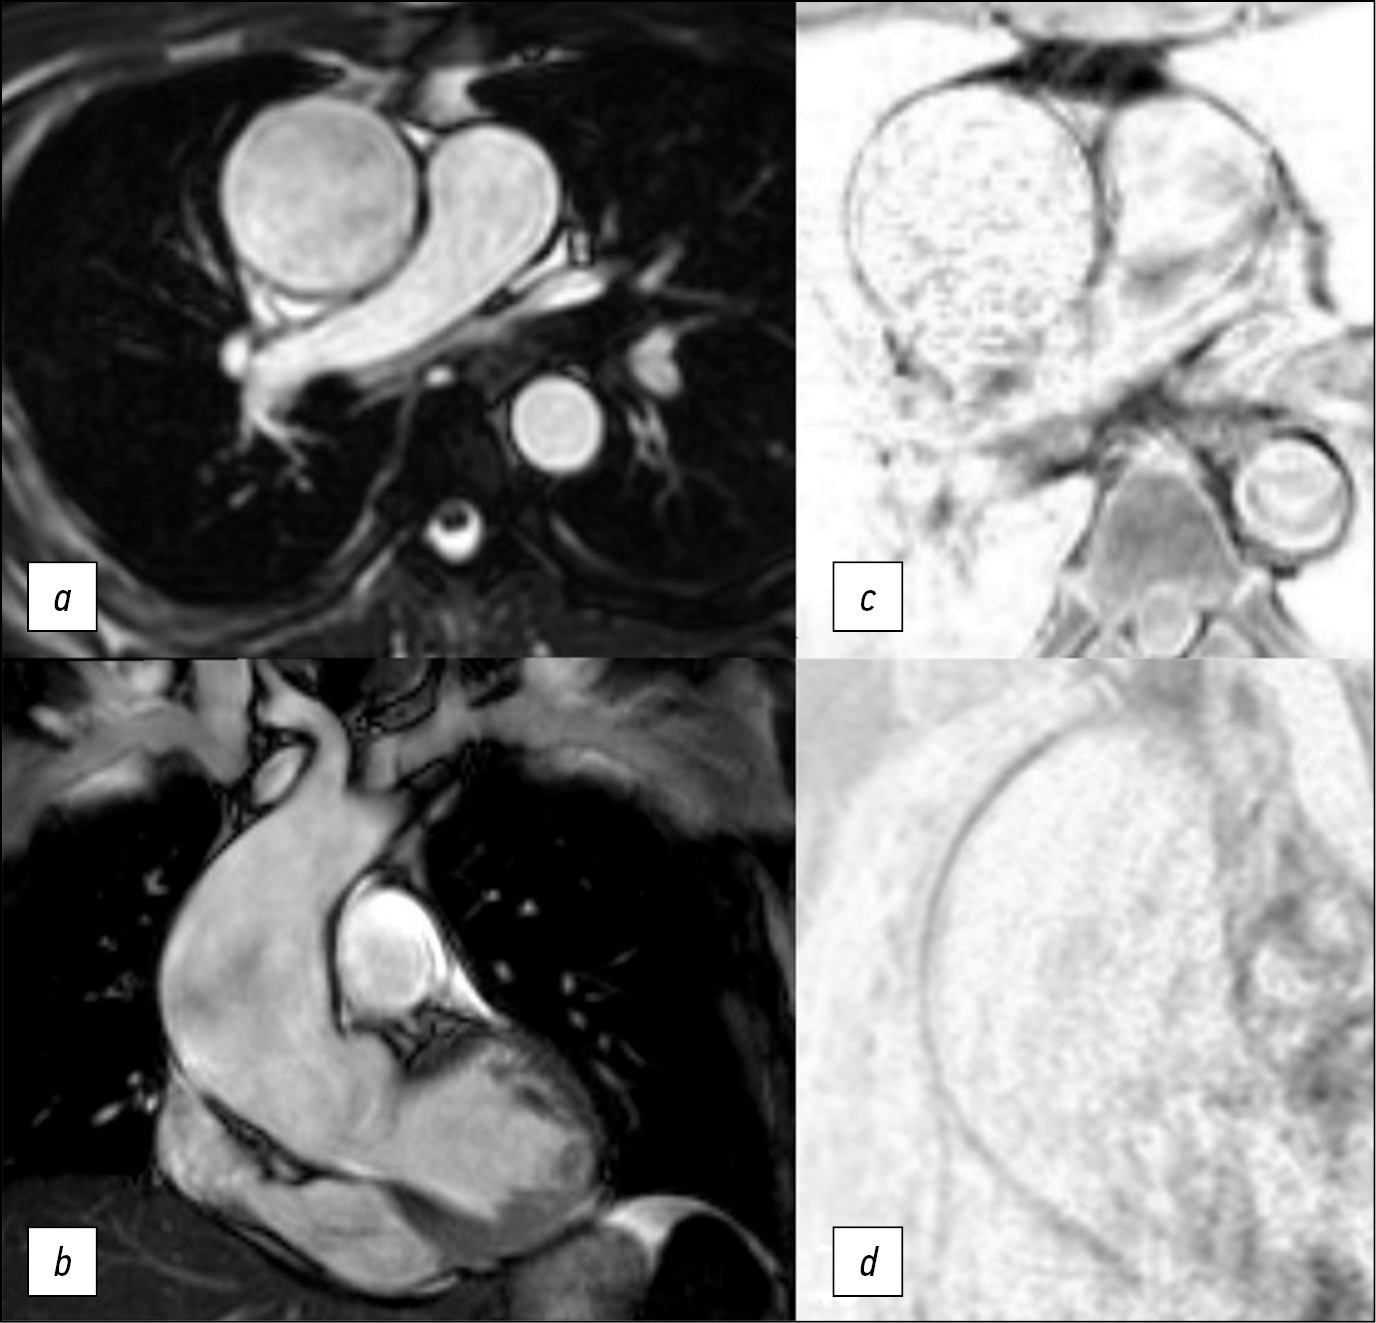

Diagnostic challenge: innovative approach in use of magnetic resonance imaging in aortic aneurysm

Аннотация

Here we report a case of technological innovation: the use of magnetic resonance imaging to determine surgical strategy.

Here is a 47-year-old man who underwent an magnetic resonance imaging and subsequent surgical treatment of the aortic aneurysm. Unlike echocardiography, magnetic resonance imaging enabled us to view the entire thoracic aorta. Unlike computer tomography, magnetic resonance imaging enabled us to detect changes in the aortic wall accurately. Thus, in this case, the use of magnetic resonance imaging allowed us to determine the distal resection edge. The patient`s postoperative course was unremarkable. Use of electrocardiogram-synchronized magnetic resonance imaging of thoracic aorta allows detecting structural changes of the aortic wall and its mechanical properties. It is significant that magnetic resonance imaging results of the aortic wall correlate with histologic examination.

The extent of changes in the aortic wall must be determined to accurately plan surgical treatment of patients with aortic aneurism.

Magnetic resonance imaging of the aortic wall is promising for further study in multicenter research.